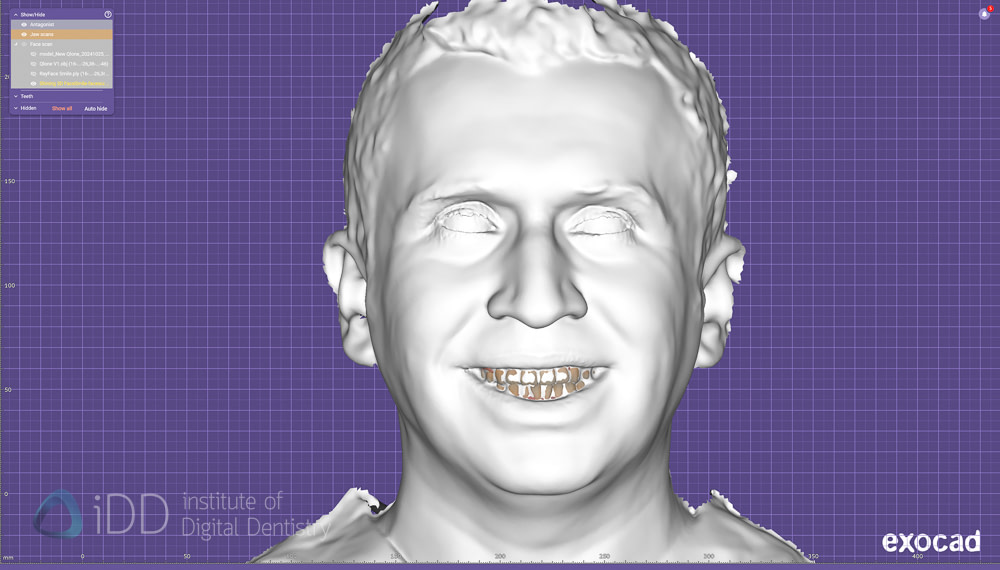

Comparing Face Scanners in exocad.

So after taking face scans with RayFace, Metismile, Qlone (original) and Qlone Dental Pro app, I brought them all into exocad to compare 2 main things - one, are there many differences between the scanners and two, how easy is it to align with IOS (the most important thing).

First thing is first - you can immediately notice the texture (colour) difference between them all. Each algorithm will work differently and interestingly there is a difference between the new Qlone app and the old Qlone app - albeit slight.

As mentioned above, the colour doesn't mean a lot at all. These scans only serve a purpose if we can align IOS with them, so we must disable colors and examine the definition on the teeth - as aligning IOS and face scans is similar to aligning any other data sets in digital dentistry - by identifying common points in both.

One interesting thing to note is that it was much easier to get a 'big smile' captured with RayFace as it is a single shoot camera essentially. So you can tell the patient to smile wide and capture that immediately. Whereas with other scanners that take between 15-60 seconds to finish the scan, often patients while smile hard at the start and then the smile will drop with time.

A few things stick out straight away. Obviously the dental specific scanners like RayFace and Metismile do the best. Very good details especially by RayFace but MetiSmile also did well and is one quarter of the cost.

Aligning the IOS data to the face scan data is simple - by choosing multiple points of reference on both data sets. You are trying to find the same points on both the IOS and face scan, so the clearer the face scan, the easier and more accurate this is.

Therefore, the better the details of the teeth on the face scan, the more likely it is going to be an accurate alignment. And if you're going to rely on this for your cosmetic wax up etc, you want this as accurate as possible.

After aligning IOS and face scan data:

RayFace

MetiSmile

Qlone Dental Pro

Regarding alignment, none were 'perfect'. There is little doubt the RayFace and Metismile gave me the most confidence that the alignment is as close as possible given the better and more clearer teeth morphology that is scanned by them.

These are all 4 face scans all aligned together. As you can see there are some differences between them. Overall, I was surprised to see that the iPhone apps can achieve similar geometry compared to the other more specialised devices. The differences are not hugely significant in my opinion and would be far more accurate than using 2D photograph.